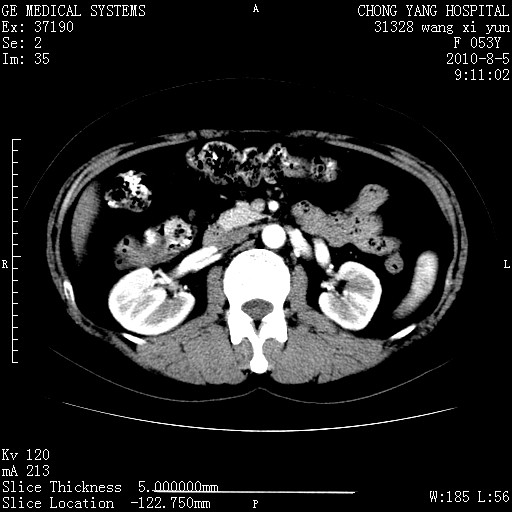

标题: CT28214:F41Y 血尿二十天,建议盆腔平扫加增强。

1)考虑肝左叶胆管细胞癌。2)脂肪肝。

支持胆管细胞ca。